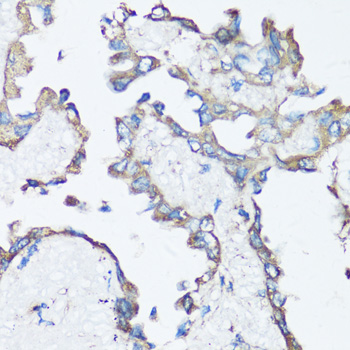

Immunohistochemistry of paraffin-embedded human lung cancer using SRC antibody.

Immunohistochemistry of paraffin-embedded human breast cancer using SRC antibody. |